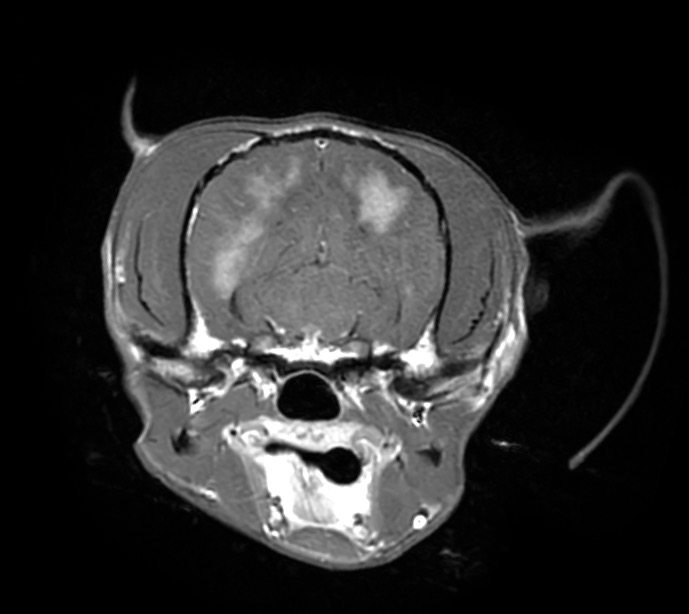

頭部MRI検査では重度の脳圧亢進所見(脳の浮腫)、大脳の後頭葉領域に炎症所見が認められ、脳炎(特に肉芽腫性髄膜脳脊髄炎:GME)が第一に疑われるという結果でしたが、

脳圧亢進所見が重度のため脳脊髄液(CSF)検査が実施できず、確定診断には至りませんでした。